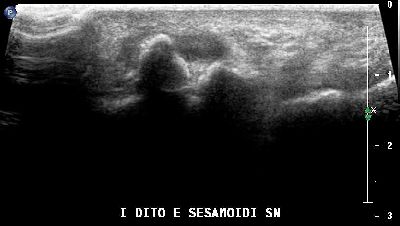

Ipoplasia dei sesamoidi del primo dito (img. 01) Ipoplasia dei sesamoidi del primo dito (img. 01)

Ipoplasia dei sesamoidi del primo dito (img. 02) Ipoplasia dei sesamoidi del primo dito (img. 02)